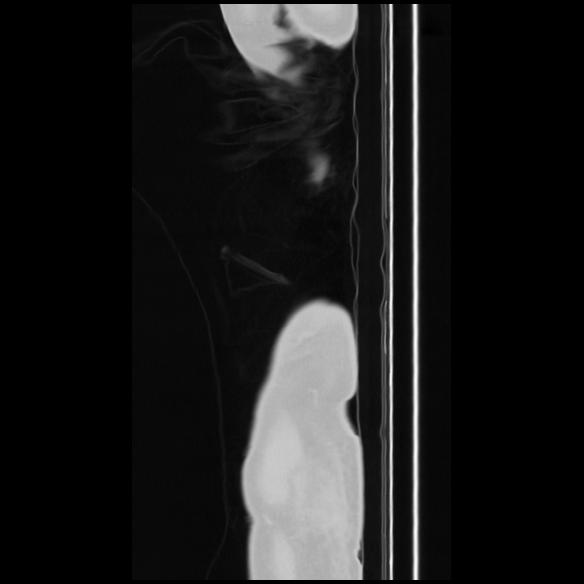

7 CUERPO,CE,Sagittal,3.000,CUERPO,Sagittal,